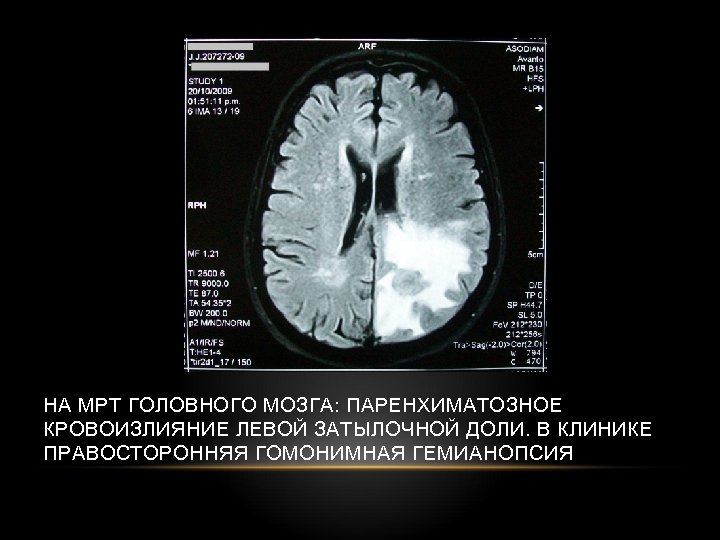

НА МРТ ГОЛОВНОГО МОЗГА: ПАРЕНХИМАТОЗНОЕ КРОВОИЗЛИЯНИЕ ЛЕВОЙ ЗАТЫЛОЧНОЙ ДОЛИ. В КЛИНИКЕ ПРАВОСТОРОННЯЯ ГОМОНИМНАЯ ГЕМИАНОПСИЯ

НАРУШЕНИЕ ФУНКЦИИ ЗРИТЕЛЬНОГО НЕРВА • Амавроз: полный перерыв проводимости зрительного нерва с развитием слепоты пораженного глаза • Амблиопия: Понижение зрения • Скотома: поражение только части волокон зрительного нерва (выпадение полей зрения секторами или островками. • Гемианопсия: Двухстороннее выпадение полей зрения: 1. Гомонимная гемианопсия 2. Гетеронимная биназальная гемианопсия 3. Гетеронимная битемпоральная гемианопсия